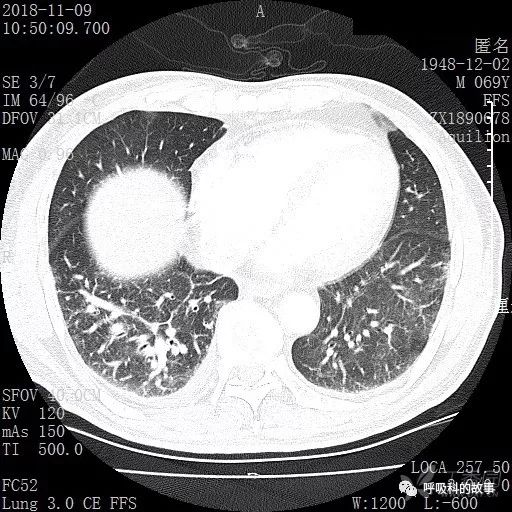

胸部增强CT示右肺门占位伴远端阻塞性肺炎,纵膈、右肺门、右侧颈根部、右侧腋下及肝门部肿大淋巴结。两侧胸腔少量积液。

肺窗CT